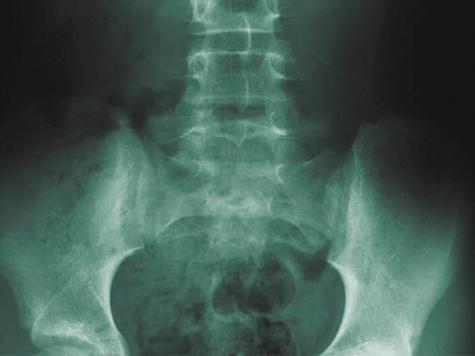

Различают два типа остеопороза: первичный и вторичный. Первичный (85% случаев) характерен для пожилых людей. С возрастом происходит нарушение структуры ткани костей: на снимке больного видно, что его кости будто источены червями. Более всего остеопорозу подвержены женщины, и чаще всего после наступления менопаузы: в возрасте 50—70 лет это заболевание у женщин встречается в 6 раз чаще, чем у мужчин. Вторичный остеопороз возникает на фоне длительно текущих заболеваний, например, ревматоидного артрита, болезней щитовидной железы, крови, почек или приема ряда препаратов.